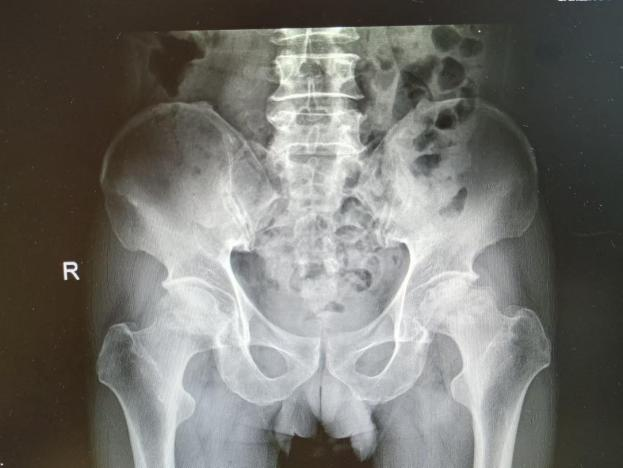

4月23日,贵州航天医院第58次晨读会由我院骨科副主任医师张艳金作学术交流,他以“加速康复指导下的快速手术”为题,详细讲解了老年股骨粗隆间骨折与儿童四肢骨折的临床诊疗难点,结合加速康复外科(ERAS)核心理念,重点阐述了ERAS理念在两大人群中的创新实践,实现患者入院后6至24小时内即可接受手术治疗。针对老年髋部骨折患者,提出通过多学科协作(MDT)与微创手术优化围术期管理,在确保安全前提下缩短术前等待时间,实施精准化麻醉及术后康复方案,可有效降低并发症发生率、改善患者生活质量和预后效果。在儿童骨折领域,强调微创术式与心理干预并行的双轨策略,既减少手术创伤对骨骼发育的影响,同时关注患儿心理疏导,实现生理功能与心理健康同步康复。并通过典型案例的影像学资料与随访数据,直观展示了ERAS理念指导下骨科治疗模式的创新成果。 贵州航天医院骨科 专家简介 赵学平 中共党员,骨科党支部书记、主任,主任医师 临床擅长:从事骨科临床工作30余年,对骨科常见疾病的诊治具有丰富的临床经验。 世界中医药联合会脊柱康复专业委员会常务理事,中华中医药学会整脊分会常务委员,中国中西医结合学会骨伤科分会肢体矫形功能重建与康复专家委员会常务委员,中国研究性医院学会骨科创新与转换专业委员会关节外科学组保髋工作委员会常委,中国康复技术转化及发展促进会骨外科与康复技术转化专业委员会常务委员,泛珠三角区域运动医学联盟(PPRD-SMA)理事会常务理事,中国研究型医院学会运动医学专业委员会委员,贵州省中医药学会整脊分会副主任委员,贵州省中西医结合学会银质针专业委员会副主任委员,贵州省康复医学会骨与关节专业委员会常务委员,贵州省人民医院骨科专科联盟常务理事,贵州省康复医学会骨内科专业委员会常务委员,中华医学会贵州省骨科学会委员,贵州省康复医学会脊柱脊髓专业委员会常务委员,贵州省运动医学分会委员,贵州省康复医学会骨与软组织肿瘤专业委员会委员,遵义市医学会创伤分会副主任委员,贵州省康复医学会骨内科专业委员会遵义地区分会常务委员,遵义市医疗事故鉴定、伤残鉴定、工伤鉴定、司法鉴定专家。 长期从事骨科临床研究及教学工作,在国家级、省部级杂志发表论文20余篇,SCI论文2篇,参与主编骨科专著2部,主持省部级科研项目2项,参与指导省部级、市级科研项目6项。 陈明勇 骨科副主任,副主任医师 临床擅长:从事创伤骨科工作约20年,对骨缺损、骨不连、骨肿瘤、肢体畸形等的肢体矫形重建及功能重建,慢性化脓性骨髓炎的根治治疗、糖尿病足的保肢治疗、快速康复理念(ERAS)下的老年骨折的诊治,四肢复杂骨折的诊治,四肢骨折等微创手术治疗具有丰富的临床经验。 2004年毕业于遵义医学院临床专业,曾在中国人民解放军总医院、广西医科大学第一附属医院、上海第六人民医院骨科进修。中国中西医结合学会骨伤科专业委员会横向骨搬移治疗糖尿病足及微血管网再生学组首届委员,遵义市医学会创伤分会常务委员。 瞿 辉 中共党员,骨科副主任医师 临床擅长:对骨科的常见病、关节外科、脊柱外科及运动医学疾病的诊治具有丰富的临床经验,熟练掌握骨科手术操作技术。 毕业于遵义医学院临床医学系,2005年前往广州中山大学第一附院骨显微医学部进修学习,2011年前往成都华西医院进修学习,并多次在省内外学习骨科相关知识,是中华医学会骨科分会会员。 赵兴东 骨科主任医师 临床擅长:擅长骨科的常见病及各种创伤、四肢骨折创伤修复、骨感染、手足疾病的诊治和手足体表畸形的矫形整复,熟练掌握骨科四肢骨病及创伤的手术操作技术,尤其在四肢关节复杂性损伤、手足外伤、组织缺损创面、难治创面的皮瓣修复方面及平足、高弓足矫形方面及四肢慢性疼痛诊治、康复方面具有丰富的临床经验。 硕士研究生,毕业于遵义医学院临床外科系,2015年前往山东省立医院手足外科进修学习;遵义市医学分会创伤分会第一、二届委员,遵义市手外科医学会第二委届员会常务委员;在省级及省级以上期刊发表文章9篇,参编著作2部,参与主持并完成市级课题1项,参与市级课题2项、省级课题1项。 张艳金 中共党员,骨科副主任医师 临床擅长:从事骨外科工作16年,对复合伤、多发伤的救治、四肢骨干骨折、关节周围骨折、骨肿瘤、骨髓炎等诊治具有丰富的临床经验。 中共党员,硕士研究生,2006年本科毕业于山西医科大学第二临床医学院,2011年研究生毕业于北京军区总医院;在“老年COPD患者合并髋部骨折的诊治”国际合作课题组研究两年,在老年髋部骨折的诊治方面具有丰富的经验,并发表论文6篇;主持遵义市级课题1项,承担遵义医科大学的临床教学工作,获得遵义医科大学优秀带教老师荣誉。编撰有《骨科疾病诊疗精粹》一书,开展2项新技术,编撰地方规范《务川自治县创伤骨科常见疾病诊疗规范》一书。 张俊凯 骨科副主任医师 临床擅长:从事骨科临床工作28年,对创伤骨折、骨感染、骨缺损、骨不连等外科诊治,四肢骨折的微创手术治疗,四肢复杂骨折(如关节内粉碎性骨折、多发骨折等)的损伤控制及手术治疗等具有丰富的临床经验。 1995年毕业于遵义医学院临床专业,2009年前往复旦大学附属医院骨科进修1年。 卢懿明 中共党员,骨科副主任医师 临床擅长:从事骨科工作18年,对创伤骨折、四肢骨折的微创手术治疗、四肢复杂骨折(如关节内粉碎性骨折、多发骨折等)的损伤控制及手术治疗,尤其是髋部骨折的PFNA等微创技术,踝关节骨折、膝关节周围骨折的Mipo微创技术等具有丰富的临床经验,开展了4项新技术,发明6项新型专利技术。 2005年毕业于遵义医学院临床专业,2017年,前往南方医科大学第三附属医院骨科进修半年,回院后运用Mipo技术对骨干骨折及干骺端骨折的治疗技术,同时积极开展骨盆骨折、髋臼骨折腹直肌外侧切口的应用;发表了多篇专业论文,经常参与省内外学术交流会授课,获得医院荣誉称号多个。 邬夏荣 骨科副主任医师 临床擅长:从事骨科工作16年,对四肢复杂骨折、骨肿瘤的诊治,尤其是足踝创伤、慢性踝关节损伤、平足症等诊疗具有丰富的临床经验。 2006年毕业于遵义医科大学临床医学专业,曾在陆军军医大学西南医院进修学习,发表多篇骨科学术论文。 余德怀 中共党员,骨科副主任医师 临床擅长:从事骨科工作10余年,对运动医学、骨关节、脊柱外科常见病、多发病的诊治具有丰富的临床经验。 硕士研究生,2011年毕业于遵义医学院临床医学专业,曾前往遵义医科大学附属医院运动医学专业进修学习;是贵州省医学会运动医学分会青年委员,西部关节镜联盟委员;发表多篇骨科学术论文。 冯 乾 骨科副主任医师 临床擅长:从事骨科工作近20年,熟练掌握骨科多发病及常见病的诊治,尤其对脊柱退变性疾病的诊断及治疗具有丰富的临床经验,主要研究脊柱微创相关治疗方式,能熟练开展椎间孔镜及UBE。 曾前往北京大学第三医院进修学习疼痛及椎间孔镜、首都医科大学友谊医院专业进修脊柱内镜;是贵州省康复医学会第三届脊柱脊髓专业委员会委员;发明专利3项、发表脊柱外科专业论文多篇。 赵小锋 中共党员,骨科副主任医师 临床擅长:从事骨科临床工作11年,对骨科常见病、多发病诊疗有较为丰富的临床经验,擅长脊柱相关疾病诊断及治疗,尤其是颈、腰、腿疼痛疾病诊断及治疗,擅长胸腰椎骨折微创经皮穿刺内固定术、经皮穿刺椎体成形术、经皮穿刺脊柱内镜下腰椎间盘摘除术、单纯开创腰椎间盘摘除术、腰椎滑脱复位椎间植骨椎融合内固定术、腰椎管狭窄减压融合内固定术及人工髋、膝关节置换术等。 2012年毕业于遵义医学院外科学专业硕士研究生,2019年参加“遵义市115医学人才精英计划”于上海交通大学第一附属医院培训学习,2023年于北京大学第三人民医院脊柱外科进修学习,曾获得遵义市优秀医师荣誉称号。 遵义市手外科第一届委员,遵义市医学会创伤分会第一届委员,遵义市医学会创伤分会第二届委员,贵州省康复医学会第三届脊柱脊髓专业会委员,遵义市医学会烧伤与整形外科学分会委员,发表论文5篇,其中国家级核心期刊1篇,SCI论文1篇,主持市级课题1项并结题,参与市级课题2项。 贵州航天医院骨科 简介 基本情况 贵州航天医院骨科组建于20世纪60年代,前身是以创伤和断肢(断指)再植闻名于世的上海市第六人民医院骨科,中国断肢(断指)再植的奠基者、中科院院士陈仲伟等著名专家、学者多次莅临科室指导医疗、教学,是贵州省最早拥有专业骨科技术科室之一,在70年代开展了贵州省首例断肢(断指)再植手术。组建50余年来,诊治患者已逾百万,挽救了无数的伤病员,成为了保障遵义地区人民群众健康的重要支撑。 经过几代人的不懈努力,今天的骨科,已由创伤骨科发展至骨病、骨肿瘤、骨结核等领域,现有脊柱外科、关节外科、四肢创伤、手足外科四个亚专科,成为了集医疗、教学、科研于一体的综合学科,是贵州省临床重点专科、遵义市临床重点专科、遵义市骨科临床医学中心、遵义市基层骨科专科联盟理事长单位。 科室目前开放床位110张,共有医护人员50余人,副高级以上专家18人,硕士研究生15人。拥有一流骨科医疗设备多台,每年不定期选派优秀技术骨干到全国各大知名医学院校进修、学习、参观、交流,并邀请国内、国外知名专家教授来院进行交流、指导,通过不断引进国内外先进的诊疗技术,科室医疗技术水平稳步提升,为广大人民群众提供了优质的医疗服务。 专科特色 骨一科 (一)骨缺损、骨不连的肢体与功能重建 胫骨横向骨搬移技术治疗糖尿病足: (二)慢性骨髓炎的根治治疗 (三)肢体缺血性疾病如糖尿病足、脉管炎的保肢治疗 (四)皮瓣修复 (五)复杂创伤的治疗 (六)老年髋部骨折及小儿骨折快速手术 老年髋部骨折: 骨二科 (一)胸腰椎骨折微创经皮椎弓根螺钉固定术 (二)老年性骨质疏松性患者腰椎滑脱脊柱内固定术(骨水泥螺钉) (三)V形双通道脊柱内镜技术(VBE)腰椎融合术治疗腰椎退行性疾病 (四)老年性骨质疏松性骨折(PVP/PKP)术 (五)人工髋关节置换术 (六)双侧股骨头坏死人工全髋关节置换 (七)右侧全髋置换术后假体周围骨折翻修 (八)人工膝关节置换术 (九)人工膝关节假体松动翻修 (十)关节镜技术 传统手术切口 关节镜技术切口 诊疗范围 骨一科 1.四肢创伤、矫形。 2.手、足踝外科。 骨二科 end